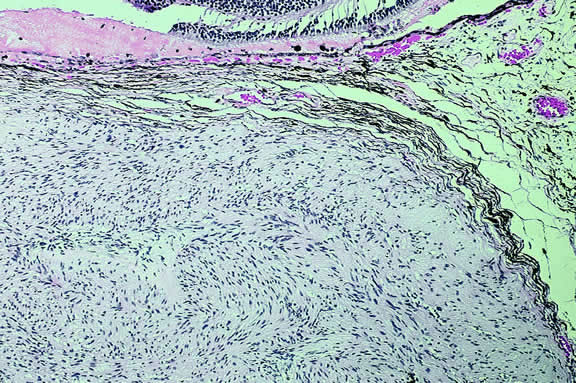

About 3% of melanomas have a diffuse growth pattern. These relatively flat tumors grow laterally without thickening the choroid.86,87 Most are about 2 mm in thickness. Diffuse melanomas often are of mixed cell type and, compared with localized lesions, are more apt to infiltrate the sclera and invade the optic nerve or orbit (Fig. 26). Delayed diagnosis or misdiagnosis is common.

Fig. 26. Diffuse choroidal melanoma thickens choroid. Massive invasion of optic nerve is seen at left. (Hematoxylin-eosin, × 50.)